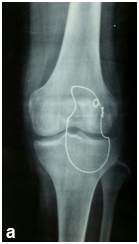

Male patient 20 years old was exposed to truma lead to avulsion of distal patellar pole Figure 1. The patient underwent management by excision of the distal pole of the patella and direct repair of the tendon to the rest of the patella. Three months later he was exposed to another truma to the knee lead to rerupture of the suture again with tense knee effusion, his seeked medical advice and aspiration was done.

• Figure 1 Preoperaive plane X-rayes shows small sized parella and very high in front of the trochles.